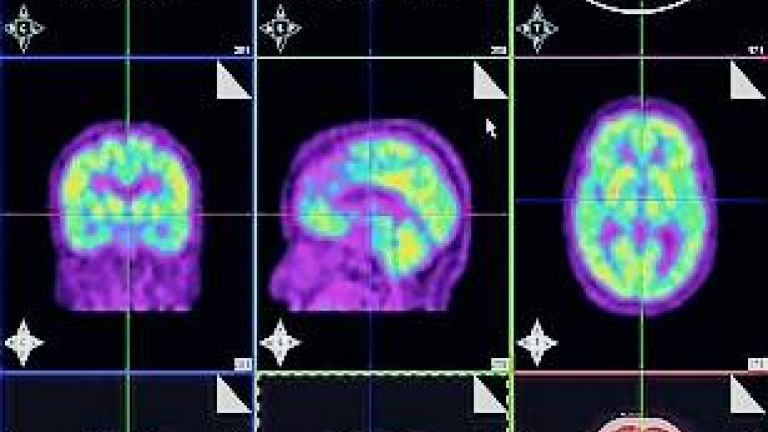

Según se publica en la última edición de JAMA, la inyección de la nueva molécula en los pacientes antes de que se les realizara una prueba de diagnóstico por imagen, un PET, localizó en la imagen cerebral la presencia de la proteína beta-amiloide, lo que se corroboró al hacer la autopsia a los 29 participantes sospechosos de tener alzhéimer después de su muerte.